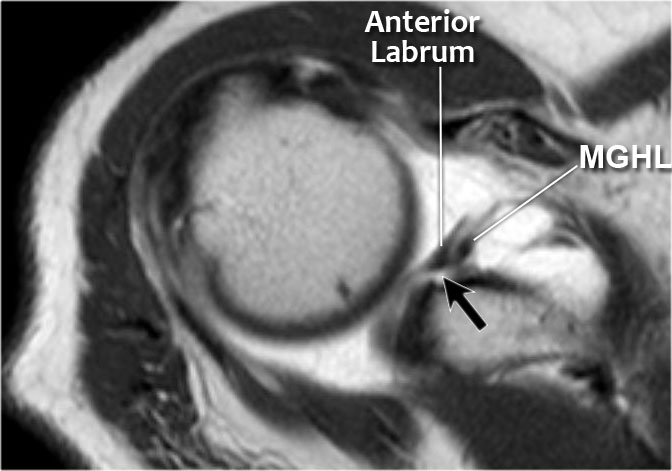

Có hình ảnh bong tách sụn viền trước-dưới (vị trí 3-6 giờ) với rách hoàn toàn màng xương bả vai phía trước.

Mũi tên chỉ vào màng xương bị gián đoạn.